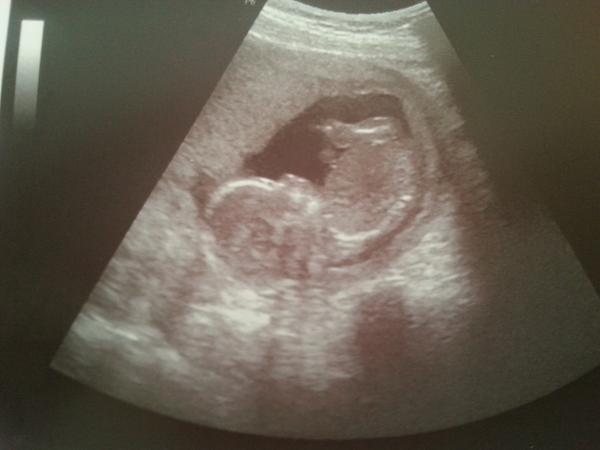

Já mám za sebou 2. screening, miminko je v pořádku... akorát se mi tam objevil myom, budou ho sledovat. Roste naštěstí směrem do bříška a neutlačuje nijak miminko

@pistalinda35 děkuji, bylo strašně roztomilý, jak se tam vrtěl a škrabal na hlavě :D na druhý screening se moc těším už teď :D hlavně, že je mimčo v pořádku a myom snad nic neudělá, ale je to děs ty komplikace. jak má být pak člověk v klidu... držím moc pěsti ať je vše ok ;)